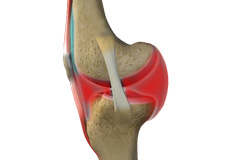

Septic Arthritis

Septic arthritis also called as infectious arthritis, is characterized by joint inflammation due to a bacterial or fungal infection that usually affects the large joints of the body such as knee or hip.